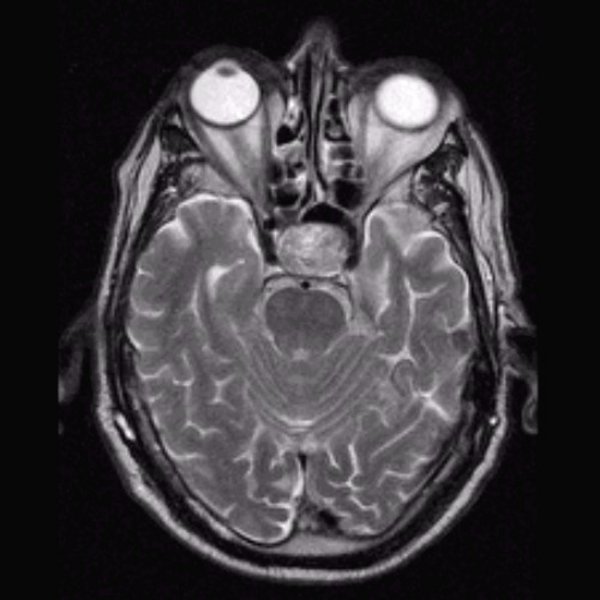

Hypophysenadenom T2 transversal